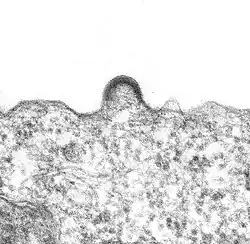

L'assemblage

Les protéines de structure du virus (matrice, capside et nucléocapside) sont produites sous forme de polyprotéines dénommées polyprécurseurs Gag. Les enzymes virales sont produites elles aussi sous forme de polyprotéines appelées Gag-Pol (Matrice-Capside-Nucléocapside-Protéase-Reverse Transcriptase - Intégrase). Lorsqu'elles sortent du Golgi, les polyprotéines Gag et Gag-Pol sont transportées vers la membrane cellulaire où elles rejoignent les glycoprotéines virales membranaires. Les domaines MA (matrice) de Gag et Gag-Pol interagissent avec la membrane, tandis que les ARN viraux sont capturés par les domaines NC (nucléocapside) de Gag et Gag-Pol. Des interactions entre les différents domaines de Gag, en particulier les capsides, permettent l'assemblage d'une structure globulaire conduisant à la formation d'une particule virale par bourgeonnement de la membrane plasmique.

Le bourgeonnement

La capside sort de la cellule infectée en arrachant une partie de la membrane cellulaire (à laquelle ont été préalablement fixées les protéines virales de surface (gp120 et gp41)).

La maturation des virus

Les particules issues du bourgeonnement sont dites immatures. Les interactions des précurseurs Gag et Gag-Pol entraînent un rapprochement de domaines (PR) dentiques de la protéase, qui vont dimériser et former une protéase active. Cette autoactivation de la protéase va entraîner la coupure des domaines PR aux alentours, et cette réaction en chaîne va permettre l'activation de toutes les protéases virales. Ces dernières vont ensuite couper les polyprécurseurs Gag et Gag-Pol entre chacun de leurs domaines. Ceci va libérer la Matrice de la Capside et de la Nucléocapside, cette dernière restant fixée sur l'ARN viral. Les protéines de capside, par leurs propriétés intrinsèques d'auto-assemblage, formeront la capside à la forme conique caractéristique. Dans cette capside : la nucléocapside, formée de l'ARN viral, des protéines de nucléocapside, de la transcriptase inverse et de l'intégrase. Cette étape de maturation virale est essentielle pour rendre les virions infectieux et prêts à infecter de nouvelles cellules.